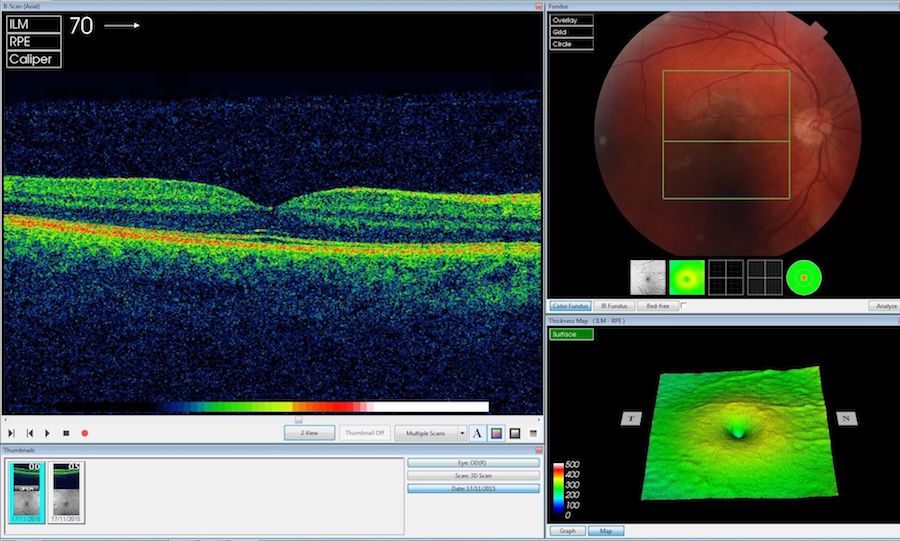

AI interpretation of OCT scans could potentially transform the management of sight-threatening eye disease. Credit: Moorfields Eye Hospital/DeepMind.